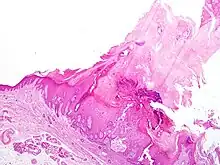

| Actinic keratosis with cutaneous horn | |

Cutaneous horn usually arises due to an underlying epidermal lesion, the most common being verruca vulgaris (wart), actinic keratosis (a potentially pre-malignant lesion of dysplastic keratinocytes), or squamous cell carcinoma (a form of skin cancer). These can look essentially identical clinically. The only reliable way to diagnose which type of lesion is present under the horn is to biopsy the lesion and have it microscopically examined by a pathologist (or dermatologist).